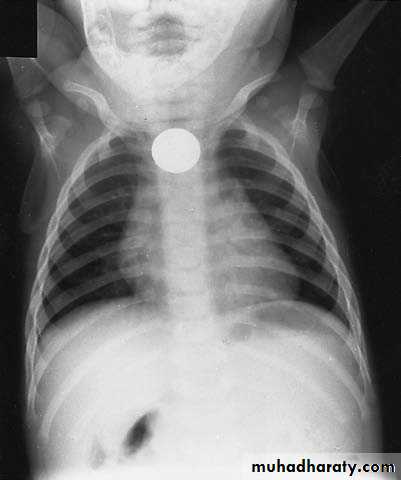

Vomiting in the First Months of Life

Diagnosis: pyloric stenosis

Presentation:• Projectile vomiting (not present in first two weeks)

• Olive mass in the abdomen

• Positive prestalsis

• FTT

Diagnosis:

• Clinically

• Ultrasound

• Ba-meal dilated stomach – failure to pass to intestine – string sign

Treatment: surgery pyloromyotomy (rami stick surgery)